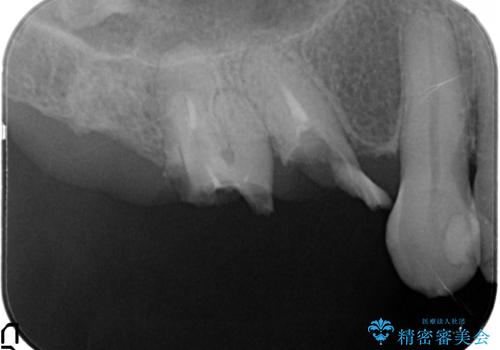

- 奥歯がとれてしまい、咬めないとのことで来院されました。

右上のかぶせ物がとれてしまい、残った根っこも虫歯になってしまっていました。

また右下の歯も虫歯と歯周病により長く使用するには難しい状態でした。